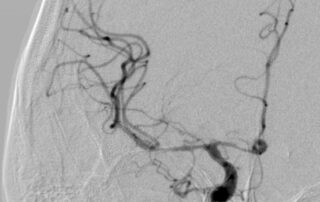

Леонтьєв Олексій2024-09-18T11:46:10+03:00До відділення звернувся пацієнт, який отримав важке вогнепальне поранення хребта та живота. Пацієнт отримав хірургічне лікування у військовому шпиталі, де також було виконано стабілізацію ушкодженого хребта. Але, [...]